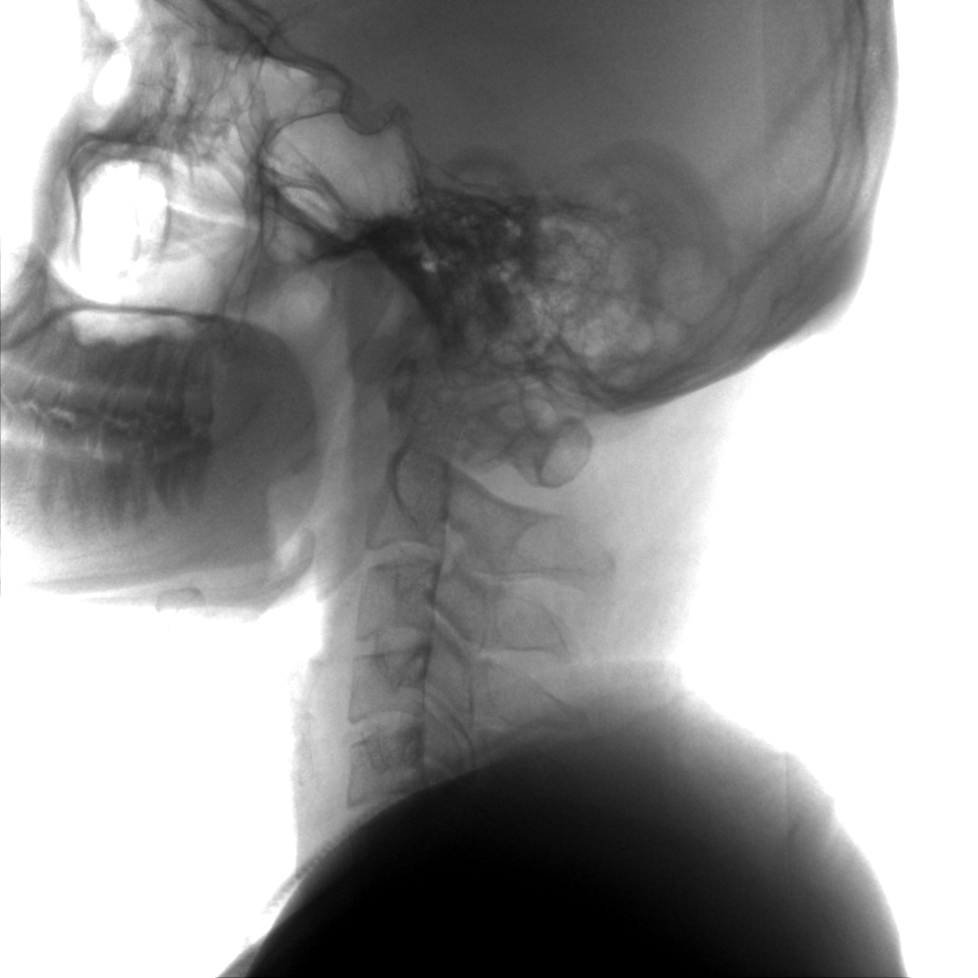

提供更大的術(shù)中三維成像視野,采集更多圖像信息,可一次拍全全段頸椎、全段腰椎、七節(jié)胸椎、雙側(cè)骶髂關(guān)節(jié)、股骨頭及單側(cè)盆骨。

在C臂掃描過(guò)程中,始終保持拍攝主體處于射線束的中心,避免了序列圖像采集過(guò)程中的橫縱方向運(yùn)動(dòng),減少相對(duì)運(yùn)動(dòng)造成的運(yùn)動(dòng)偽影。